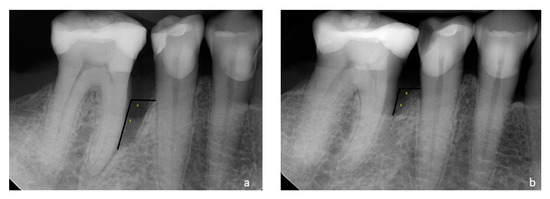

| 2 Weeks Pre Op. | 6 Months Post Op. | p *** (2 Weeks Pre Op–6 Months Post Op) | |

| R IDD (mm) | |||

| Test group | 3.53 (±0.92) | 1.65 (±0.78) | <0.00 |

| Control group | 3.43 (±0.57) | 1.57 (±1.05) | <0.00 |

| p ** | NS (p ** = 0.807) | NS (p ** = 0.87) | - |

| R IDW (mm) | |||

| Test group | 2.14 (±0.68) | 1.77 (±0.84) | <0.00 |

| Control group | 1.96 (±0.76) | 1.25 (±1.06) | <0.00 |

| p ** | NS (p ** = 0.506) | NS (p ** = 0.082) | - |